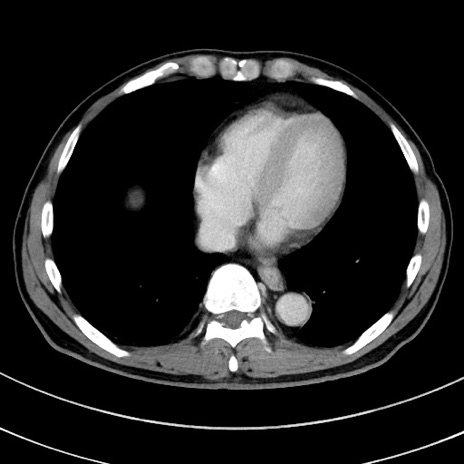

症例8(横断像)

【症例】 60歳代男性

【主訴】 黒色吐物

【現病歴】 4日前から嘔気自覚、2日前の朝食後にも嘔気あり、自分で手で嘔吐反射起こし嘔吐したところ血が混ざっていたため受診。

【既往歴】 5年前汎発性腹膜炎を伴う急性虫垂炎で手術、高血圧、前立腺肥大症、高脂血症

【身体所見】 腹部正中に手術癩痕あり 腹部平坦・軟圧痛なし膨満感あり

【データ】WBC 8400、CRP 4.54